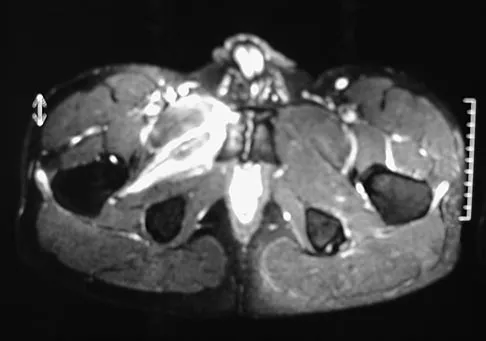

A 37-year-old woman has had intermittent paresthesias and numbness in the plantar foot for the past 6 months. She reports that the symptoms are worse with activity, and the paresthesias are beginning to awaken her at night. MRI scans are shown in Figures 6a and 6b. What is the most likely diagnosis?

Explanation

The symptoms are consistent with tarsal tunnel syndrome. Ganglion cysts are a well-known cause of tarsal tunnel syndrome. The MRI scans show a high intensity, well-circumscribed mass in the tarsal tunnel that is consistent with a fluid-filled cyst. Patients usually respond well to excision of the ganglion and resolution of the tarsal tunnel symptoms. The surrounding fat is a different signal intensity on the MRI scans, which rules out a lipoma. Synovial cell sarcoma has a heterogeneous appearance on an MRI scan. Metastatic tumors are most commonly found in the osseous structures of the foot, not the soft tissues. Rozbruch SR, Chang V, Bohne WH, et al: Ganglion cysts of the lower extremity: An analysis of 54 cases and review of the literature. Orthopedics 1998;21:141-148. Llauger J, Palmer J, Monill JM, et al: MR imaging of benign soft-tissue masses of the foot and ankle. Radiographics 1998;18:1481-1498.